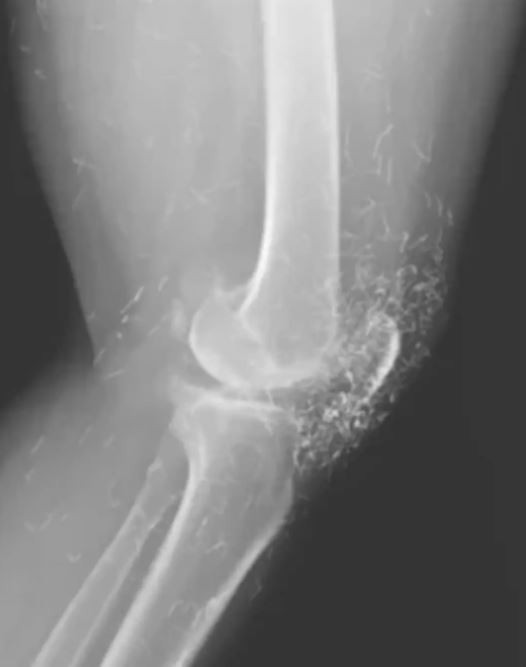

Görüntülerde ayrıca kemiklerde kalınlaşma, sertleşme ve mahmuz benzeri çıkıntılar belirlendi. Altın ipliklerin sebebinin ise alternatif bir tedavi olduğu anlaşıldı.

Hastanedeki tetkikler, röntgendeki altın ipliklerin kadının düzenli olarak yaptırdığı altın iplik akupunkturu seanslarında kasıtlı olarak bırakıldığını ortaya koydu. Bu yöntemde, steril kısa altın iplikler dokuya yerleştirilerek sürekli uyarım sağlanması hedefleniyor.

Ayrıca bu iplikler, görüntüleme teknikleri üzerinde olumsuz etkiler yaratabiliyor. Röntgen yorumlarını zorlaştırmasının yanı sıra, manyetik rezonans (MR) görüntülemelerinde ipliklerin hareket ederek damarlara zarar verme riski taşıdığı ifade edildi.

Doktorlar, bu tür geleneksel tedavilere başvuran hastalarda altın ipliklerin varlığının mutlaka dikkate alınması gerektiğini vurguluyor. Neyse ki iplikler röntgende kolayca görülüyor ve konumları takip edilebiliyor.